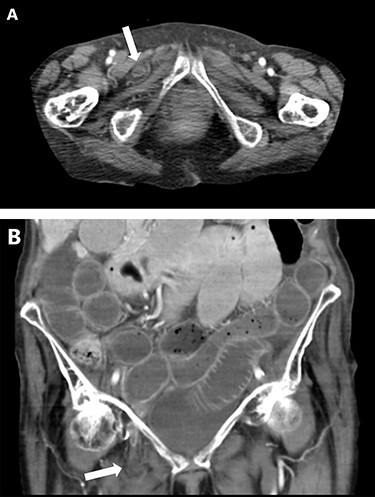

On Day 4, she developed sudden onset of abdominal distension with nausea and vomiting and an urgent surgical review followed. CT abdomen with intravenous and oral contrast demonstrated small bowel obstruction secondary to strangulated obturator hernia (Fig. 2). Repeat blood investigations revealed an elevated C-Reactive Protein (CRP) (143 mg/L) with mildly elevated lactate (1.1 mmol/L) and urea (8.9 mmol/L). Fluid resuscitation and urgent exploratory laparotomy were performed showing extensive adhesions at the proximal bowel with dilatation of small bowel and ischaemia of the herniated section. The bowel was necrotic and a 10 cm resection followed by a hand-sewn side-to-side anastomosis with direct closure of the hernia defect primarily.

CT abdomen showing small bowel obstruction with right-sided obturator hernia (white arrow) on axial (A) and coronal (B) views.